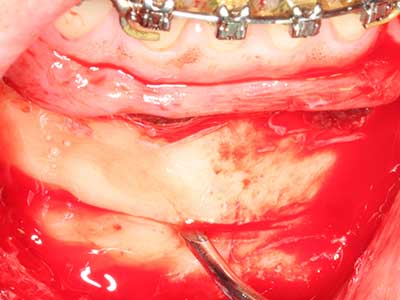

Indication: Preparations close to nerve tissue

As noted above, indications for piezo surgery can also be found in the field of conservative dental surgery. Special working tips simplify the exposure of root tips and make it easier to protect nerves and sinus mucous membranes, particularly in the lower premolar and upper posterior tooth regions. Angled diamond tips are used to precisely prepare the resection cavity for the retrograde root filler material for unsealed apical obturation. The ultrasonic technology means the tips can be very slender, which improves the view and the size of the access cavity. As a result, the application of ultrasonic surgery for this indication is one of the standard procedures for apical resection (Del Fabbro, Tsesis et al. 2010, Scarano, Artese et al. 2012).

Indication: Apical resection

When surgical procedures are performed on bone in the immediate vicinity of sensitive structures such as blood vessels or nerves, rotary instruments pose a significant risk of iatrogenic injury. Piezoelectric devices can be helpful for preparation of bone covers and removal of hard tissue close to nerves, particularly for exposure of nerves after iatrogenic injury but also during nerve lateralization for resective and reconstructive procedures or implant placement (Fig. 17-20). Light contact between the piezotip and the nerve does not generally result in damage but proceeding incautiously with saw-like motions or attachments where a residual bone substrate remains may cause temporary or even permanent nerve damage. However, the risk of damage is considered to be substantially lower than when using saws or milling instruments (Pereira, Gealh et al. 2014).